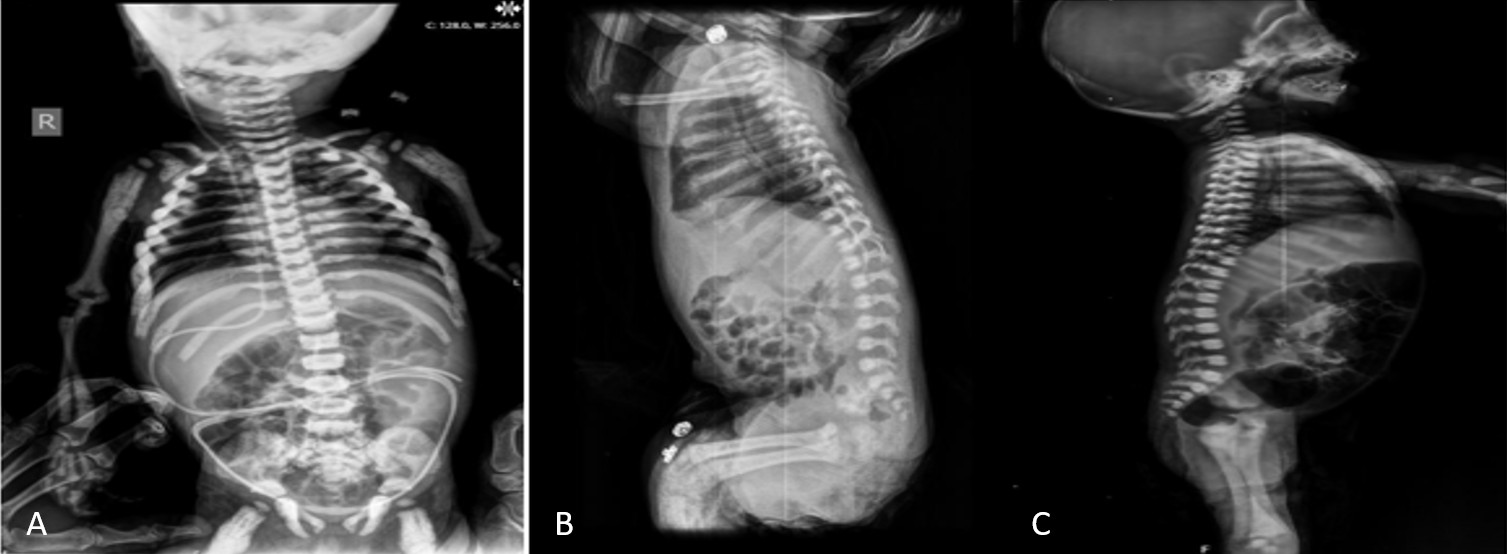

A total of 12 patients (7 female, 5 male) from ten distinct families were included. All patients were born to consanguineous parents. The median age at diagnosis was three months (range, 1 to 36.5 months). The most common presenting symptoms were nasal congestion and difficulty sucking (n=4) (Table 1). Radiographic assessments in all 12 patients revealed features typical of osteopetrosis, including diffuse bone sclerosis, thickened skull bones, a “sandwich vertebrae” appearance, and a “bone-within-bone” sign (Figure 1 and Figure 2).

Radiographic examinations typically reveal generalized osteosclerosis throughout the skeleton, characterized by a “marble bone” appearance. The notable radiologic findings are: “Erlenmeyer flask” deformity, “bone-in-bone” or “endobone” appearance, and the “sandwich vertebrae” or “rugger jersey spine”.5

This group comprised Patients 1, 2, 3, 4, 5, 6, and 7. Bone marrow failure was the predominant clinical feature. Six of the seven patients (85.7%) had anemia and/or thrombocytopenia at presentation or during follow-up. All patients in this group, except one, required transfusions, with six becoming transfusion-dependent. All seven patients had hepatosplenomegaly, indicative of extramedullary hematopoiesis. Vision loss was present in three patients, and pale optic discs were noted in six. Osteopetrorickets was diagnosed in six of the seven patients (85.7%). Neurodegenerative changes were not a feature in this group. At the time of the study, four patients in this group had died, two were alive under supportive care, and one was alive and well post-HSCT.